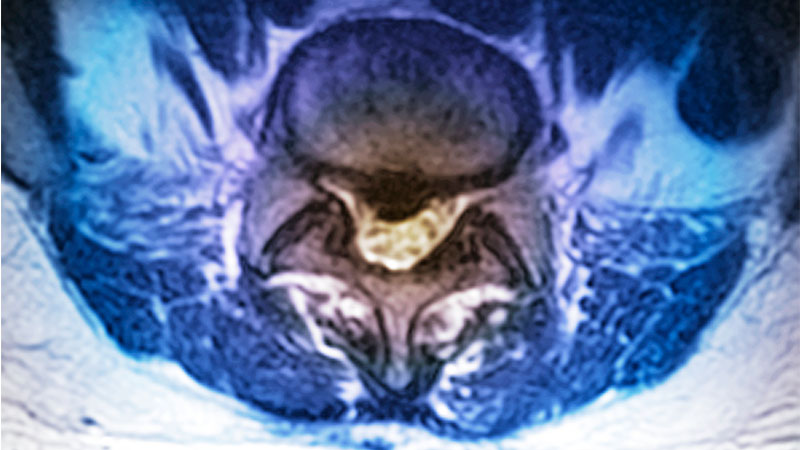

Robotic Spine Surgery: Weighing the Benefits

Seeking to expand the evidence about the use of robotics in spinal surgery, Columbia orthopedic spine surgeons have published a number of studies evaluating benefits and potential drawbacks. In a comprehensive review initially published online in the September 6, 2021 issue of Spine Deformity, the researchers evaluated the accuracy and benefit of computerized navigation and robotics for spinal deformity surgery, focusing on their impact on clinical outcomes. Their findings suggest that computer-based navigation and robotic-assisted guidance systems for pedicle cannulation provide equivalent, and in some reports, superior results, to freehand techniques in terms of radiographic accuracy. Findings of a second study, published in the September 2021 issue of The Spine Journal, which examined trends in outcomes and complications in adult patients undergoing robot-assisted surgery, suggest that robot screw accuracy, operative efficiency, reliability, and radiation exposure have improved significantly between 2015 and 2019, likely in parallel with increased surgical expertise with robots and advances in robotic technology. A third study led by Columbia faculty is the first and largest multicenter study to compare percutaneous and open approaches with robot-assisted platforms. Results are published in the January 2022 issue of Spine.

Columbia orthopedic spine surgeons provide in-depth analysis of the role of robotics in spine surgery.